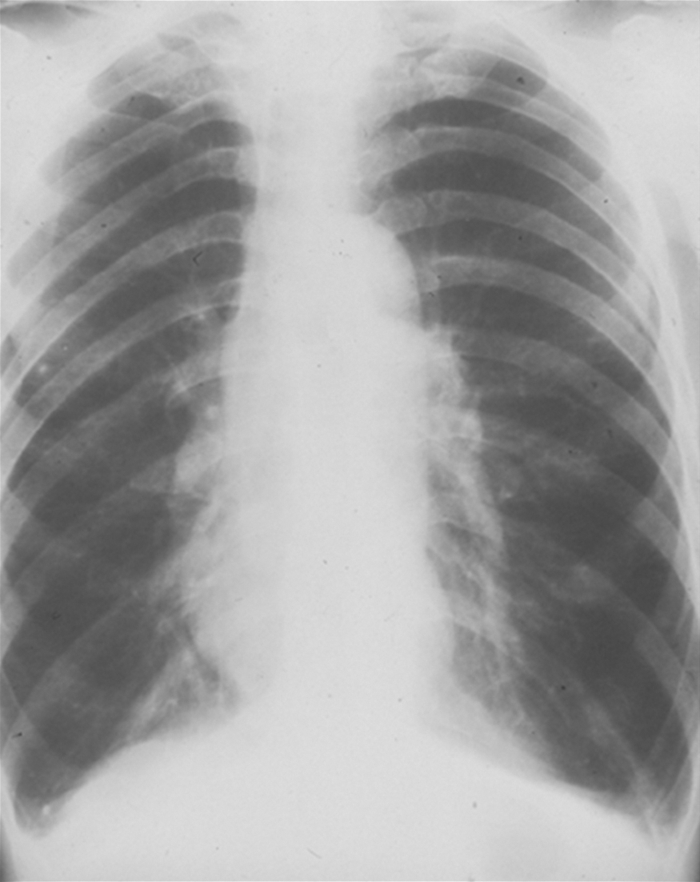

The chest x-ray film of a patient with emphysema shows flattened diaphragms and increased air spaces. The lung fields appear hyperlucent (dark), with little vascularity. The heart appears to be hanging from the great vessels (Fig. 1.3). CT scans, especially spiral CT scans, show a three-dimensional picture of enlarged air spaces and loss of supporting tissue. CT scans also delineate whether the emphysematous changes are localized or spread throughout the lungs.

Unlike the patient with emphysema, the patient with chronic bronchitis may show few clinical signs of underlying disease. Body weight may be normal or increased, with minimal changes to the chest wall. Patients with bronchitis may appear normal except for cough and dyspnea. The chest x-ray film in chronic bronchitis differs markedly from that in emphysema. The congested airways are easily visible. The heart may appear enlarged, with the pulmonary vessels prominent. The diaphragms may appear normal or flattened, depending on the degree of air trapping present. If there is right-sided heart failure, swelling (edema) of the lower extremities is often present.